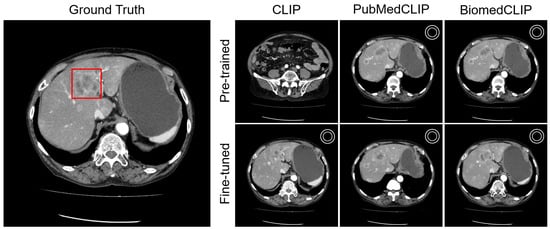

Appendix C.1. Lesion Awareness

Appendix C.2. Organ Awareness